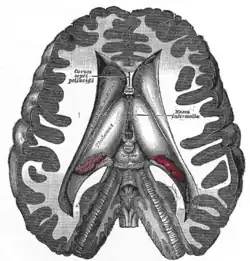

Coronal section of brain through intermediate mass of third ventricle. | |